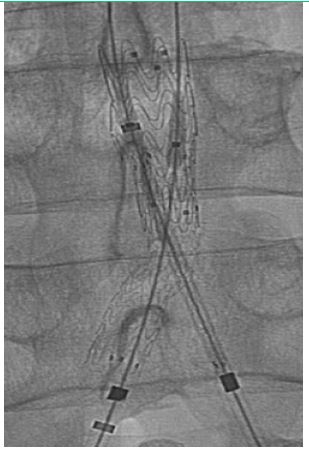

Male patient, 72 years, active smoker, with arterial hypertension, diabetes, and disabling bilateral inferior limbs claudication. The patient was submitted to endovascular surgery with an iliac kissing stent and implant of Wrapsody 9×50 mm at the right iliac common artery and Wrapsody 9×75 mm at the left common iliac artery, followed by post-dilatation with a catheter balloon. (Figure 4) The patient was discharged from the hospital first day post-operative and 1-month follow-up showed endoprosthesis patency with complete resolution of the previous symptoms.

Figure 4: Iliac kissing stent and implant of Wrapsody 9×50 mm at the right iliac common artery and Wrapsody 9×75 mm at the left common iliac artery.